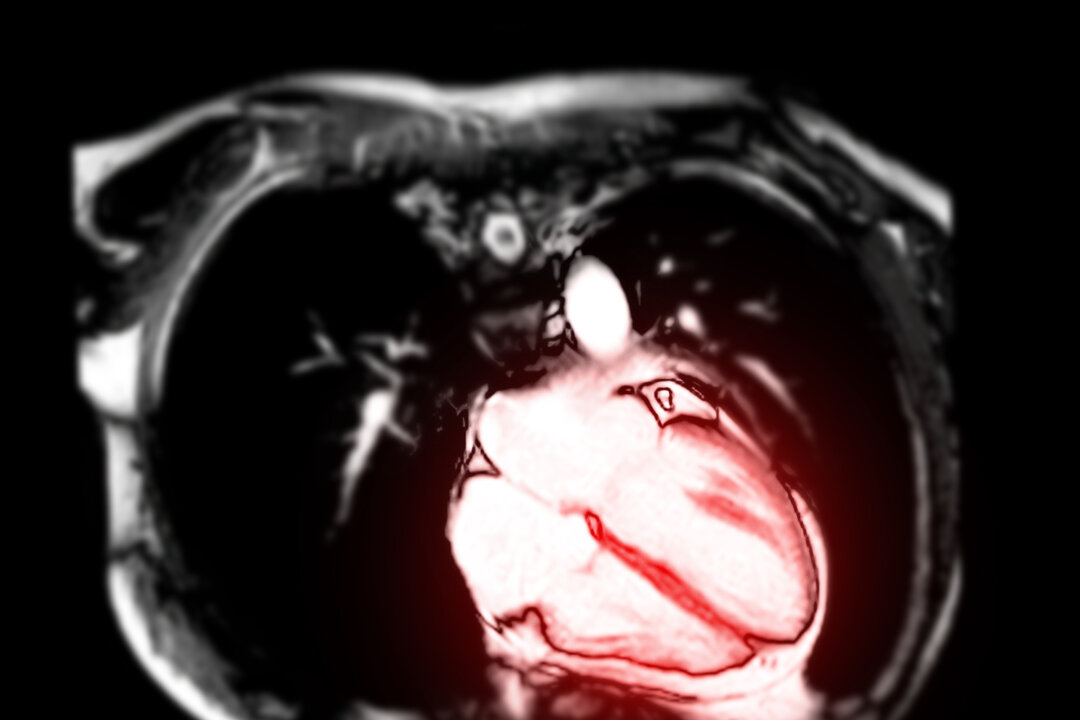

A cardiac MRI of college athletes who had COVID-19 is seven times more effective in detecting inflammation of the heart than symptom-based testing, according to a new study.

The study of 1,597 COVID-19 positive athletes in the Big Ten Conference who had cardiac magnetic resonance (CMR) screening found 2.3% were diagnosed with myocarditis and most didn’t exhibit symptoms of the rare disease, a leading cause of sudden death in competitive athletes. Of the 37 athletes diagnosed with myocarditis, 28 were asymptomatic.

The researchers found that CMR was highly effective at detecting both symptomatic and asymptomatic myocarditis as well as allowing athletes to immediately resume their sport if screenings were normal. With this protocol, 97.7% of the Big Ten athletes were cleared to return to exercise and competition.